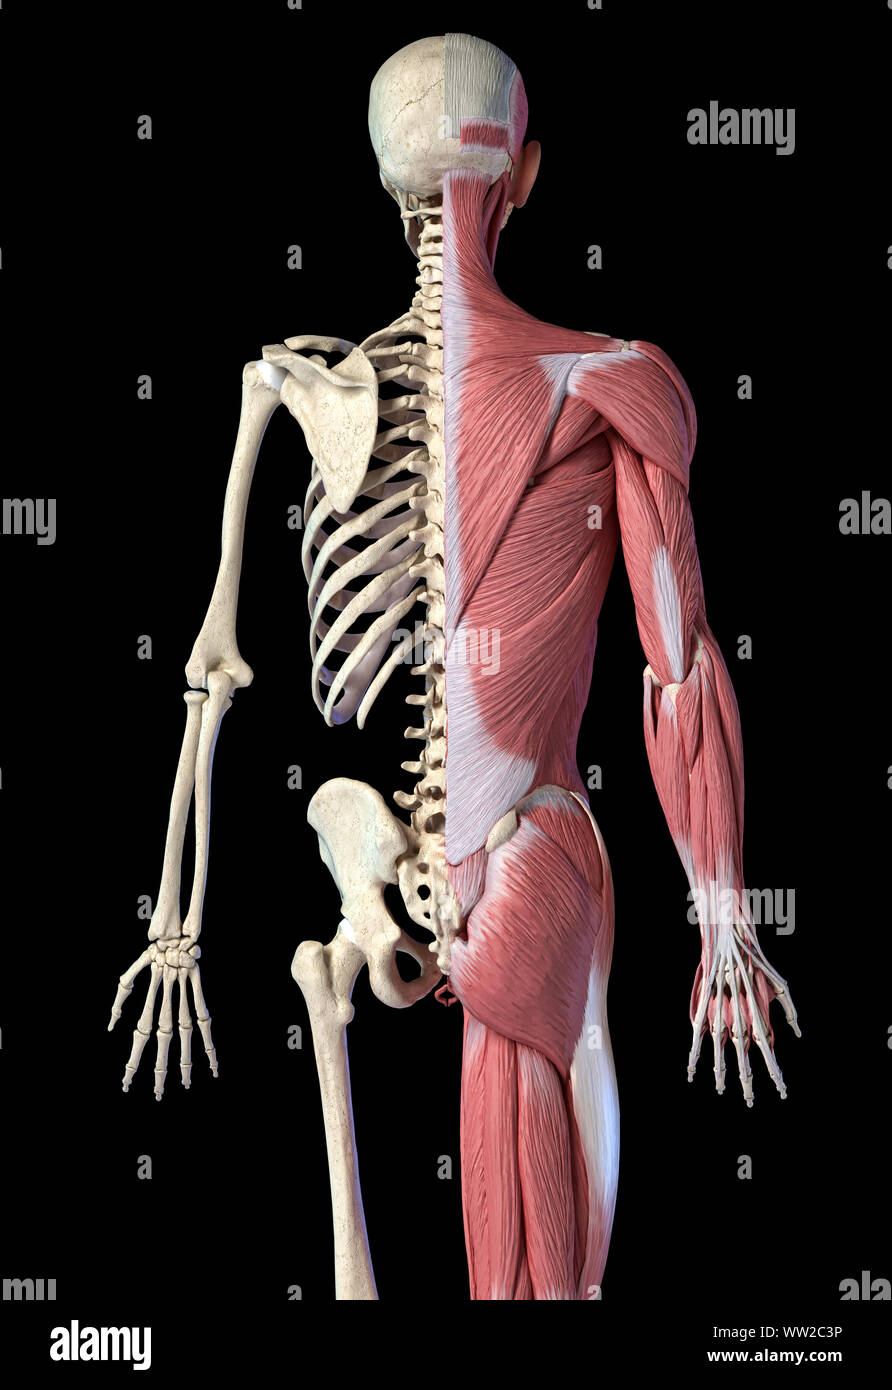

RFWW2CNW–Die männliche Anatomie, Gliedmaßen und hip Muskel- und Skeletterkrankungen Systeme, mit interner Muskelschichten. Vorder- und Rückansicht. schwarzen Hintergrund. 3d-Abbildung.

RFWW2C3P–Die männliche Anatomie, 3/4 Abbildung Muskel- und Skeletterkrankungen Systeme, Rückansicht auf schwarzen Hintergrund. 3D-Anatomie Illustration.